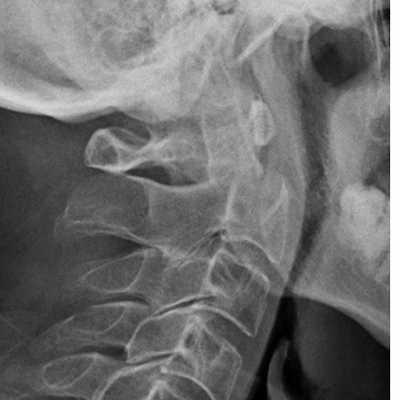

(Слева) Рентгенограмма в боковой проекции: снижение высоты переднего отдела межтелового пространства С6-С7, расширение межостистого промежутка и дистракционное повреждение дугоотростчатых суставов (смещение суставных поверхностей относительно друг друга > 50%).

(Справа) На аксиальном GRE МР-И у пациента с флексионной травмой шейного отдела позвоночника видно массивное паренхиматозное кровоизлияние в центральной части спинного мозга, характеризующееся в этом режиме низкой интенсивностью сигнала. Такая картина является плохим прогностическим признаком возможности полноценного функционального восстановления. (Слева) Рентгенограмма в боковой проекции: расширение промежутка между остистыми отростками С6 и С7. Нижний суставной отросток С6 находится впереди верхнего суставного отростка С7.